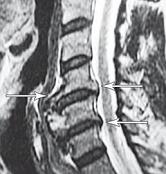

МРТ № 3

На МРТ № 3 — поясничный отдел позвоночника. (На данном «контрольном» снимке наблюдаются остаточные явления дегенеративно-дистрофического процесса в сегменте LV-SI после устранения методом вертеброревитологии секвестрированной грыжи межпозвонкового диска.)

В поясничном отделе форма позвоночного канала, создаваемая телом и дужками позвонка, вариабельна, но чаще она пятиугольная. В норме позвоночный канал в пояснично-крестцовом отделе сужен в переднезаднем диаметре на уровне LIII и LIV позвонков. Его диаметр каудально увеличивается, и поперечное сечение канала приобретает форму, близкую к треугольной, на уровне LV-SI. У женщин канал имеет тенденцию к расширению в нижней части крестцовой области. Сагиттальный диаметр значительно уменьшается от LI к LIII почти неизменен от LIII к LIV и увеличивается от LIV к LV. В норме переднезадний диаметр позвоночного канала в среднем равен 21 мм (15–25 мм).

Существует простая и удобная формула определения ширины позвоночного канала:

нормальный сагиттальный размер не менее 15 мм;

11–15 мм — относительный стеноз;

менее 10 мм — абсолютный стеноз. Уменьшение этого соотношения свидетельствует о сужении канала.

Высота поясничных межпозвонковых дисков 8–12 мм, нарастает от LI до LIV-LV, обычно уменьшается на уровне LV-SI